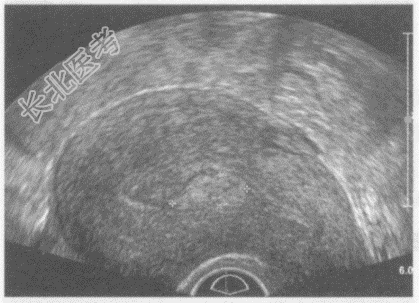

- 单项选择题临床资料:女性患者, 22岁,自述月经量增多淋漓不止。超声综合描述: 经阴道扫查子宫前位,形态大小正常, 肌层回声均匀,宫腔内可见1.7cm×0.7cm中等回声区(+…+所指), 宫腔线连续中断,CDFI: 可见彩色血流自蒂部伸入其内。见下图及彩图。超声提示: